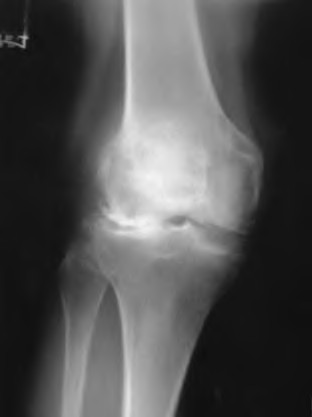

A 65-year-old woman with painful knee arthritis and the deformity seen in Figure A, is scheduled to undergo a total knee arthroplasty. All the following are risk factors for a post-operative peroneal palsy EXCEPT:

Figure A demonstrates and AP radiograph of the knee showing end-stage arthritis with severe lateral compartment narrowing.